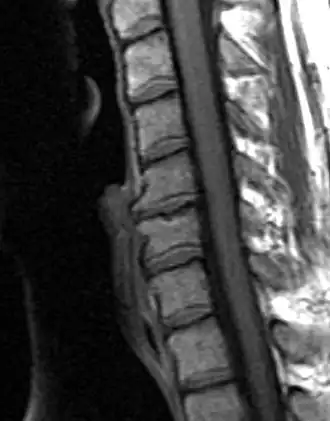

Schmorl’s Nodes

Compressive forces stressing the vertebral column as a result of mechanical loading often cause disc herniation. In turn, this facilitates the formation of cystic lesions referred to as Schmorl’s nodes on the superior and inferior vertebral endplates.[17]